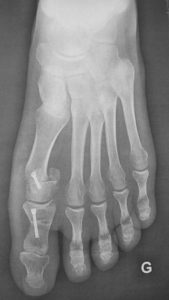

One of the pillars of modern hallux valgus surgery are the osteotomies. They are bone cuts performed by the surgeon to reorient the axis of the foot. They allow first metatarsal straightening and erase bone protrusion.

The osteotomies in open surgery are mostly of the “scarf” type or “chevron” type. To fix the bones in their new orientation, hardware is implanted : screws, staples, wires. The most often they are not necessarily to be removed as these implants are buried deep in the bone and perfectly well tolerated.

It requires dedicated instruments, specifically developed to burr the bone protrusion, cut the bone, and perform the sections of soft tissues. Of course, the direct visual control is missing, since everything is realized through very small holes. Therefore, it is replaced by a low-irradiation peroperative radiography, called fluoroscopy.